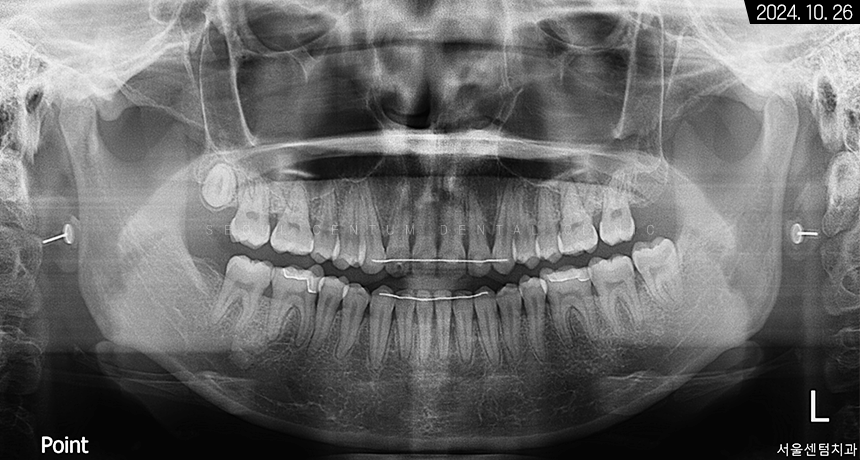

이번에 찾아오신 분의 파노라마 사진을 보면

치아가 굉장히 빽빽하게 들어차있는 것과

전형적으로 구강 내 협소한 자리로 인해

치아 전돌이 형성된 케이스라는 것을

알 수 있습니다.

하악 좌측 사랑니도 보이고

상악 우측 사랑니까지 맹출 된 것을 볼 수 있었고요.

앞니끼리 공간이 부족해 겹친 것이 확인되었고

부분적으로 치간이개를 갖고 계셔서

그 공간을 폐쇄하면서 치간 삭제를 동시에 한다면

돌출 정도가 어느 정도 해소될 것으로 예상됐습니다.

파노라마 사진으로 보면

전치부에 예쁘게 붙어있는

유지 장치를 볼 수 있습니다.

또한 초반에 보였던 치간 이개가 해소되었으며

휘어졌던 하악 앞니 치근의

수직 상태가 정상을 회복하였다는 걸 알 수 있습니다.

환자분이 발치에 대한 거부감이 있으셨기에

사랑니는 고스란히 남겨드렸습니다.